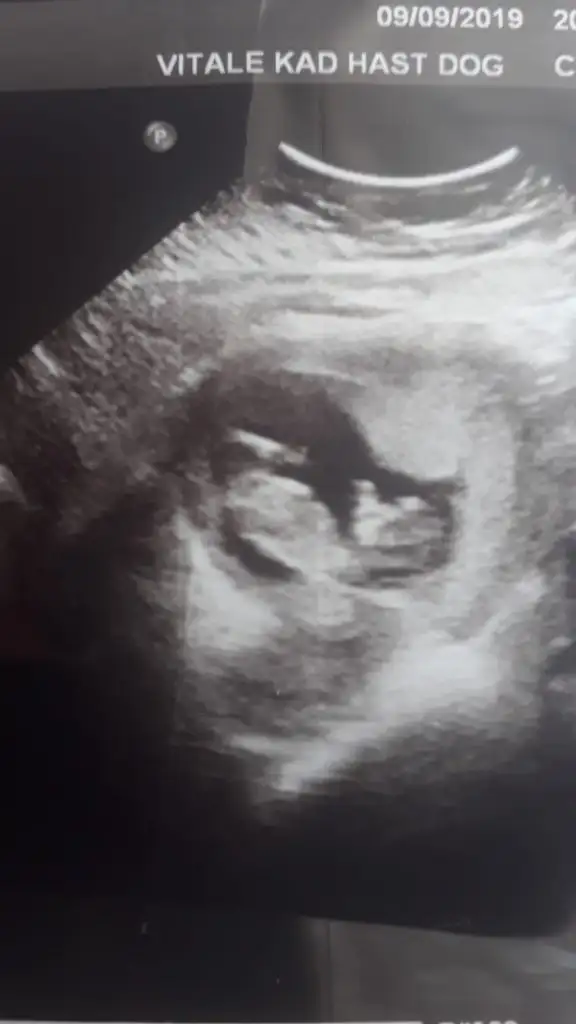

Kız gibibir fotograf karesi de bizden gelsin dr.henuz tahmin yapmadi siz neler goruyoyorsunuz

bir fotograf karesi de bizden gelsin dr.henuz tahmin yapmadi siz neler goruyoyorsunuz